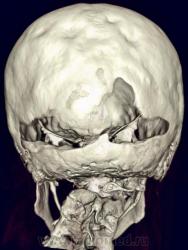

Nela. КТ головного мозга и костей. Гистиоцитоз Х (морфологическая верификация).

Пациент - молодой человек, предъявляет жалобы на головные боли и боли в шее. Болеет с 2002 года.

Гистиоцитоз Х – заболевание ретикулоцитарной системы неизвестной этиологии, морфологически характеризующееся первичной пролиферацией своеобразных гистиоцитов (клеток Лангерганса или клеток Х) и образованием в легких и в других органах и тканях гистиоцитарных гранулем и гранулематозных инфильтратов.

Заболевание относится к системным: гранулемы могут образовываться в различных органах, но наиболее часто поражаются легкие и кости. Заболевают чаще всего люди молодого возраста, между 20 и 40 годами, большей частьюмужчины.

Такое обширное поражение нечасто встречается. Я вижу впервые.

Конечно чаще, но не каждый день. Гистиоцитоз Х или эозинофильная гранулема, или гистиоцитоз из клеток Лангерганса редкое заболевание. Но, думаю, каждый рентгенолог со стажем видел костный гистиоцитоз в костях свода или в позвонке. У нас областное гематологическое отделение, поэтому наверно раз в 1-2 года встречаем.